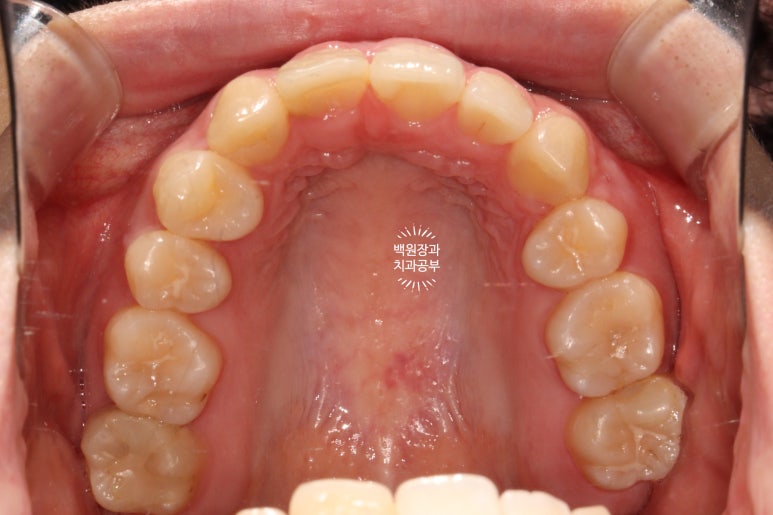

교합면에서 보면, 앞니가 다섯개라는 것이 더 명확해집니다!!!

아마, 어렸을 때 앞니를 잃어버리신 것 같아요. 그래서 작은 어금니도 비대칭으로 왼쪽은 1개 오른쪽은 2개였습니다. 상당히 난이도 있는 교정치료일텐데, 정말 훌륭한 치료결과이긴 했었어요!